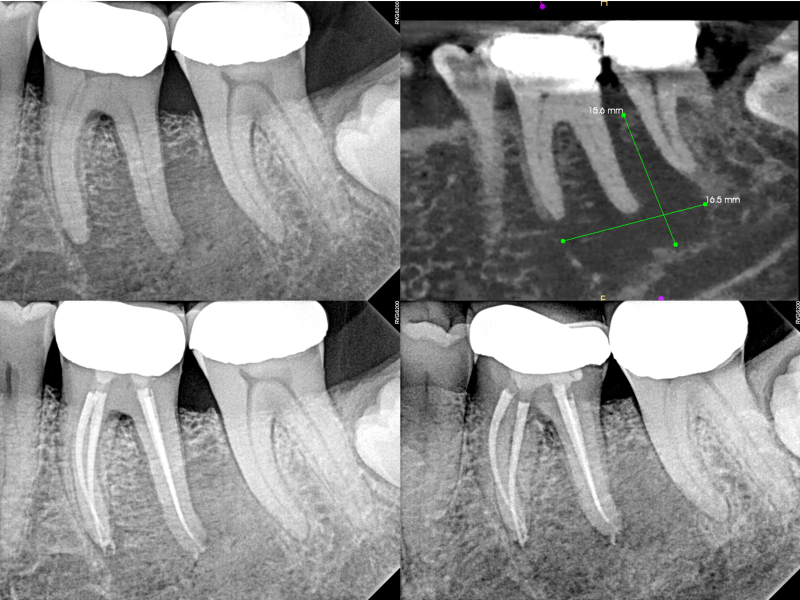

Guarded Pre-Op with Healing Evidence

Guarded Pre - Op with Healing Evidence